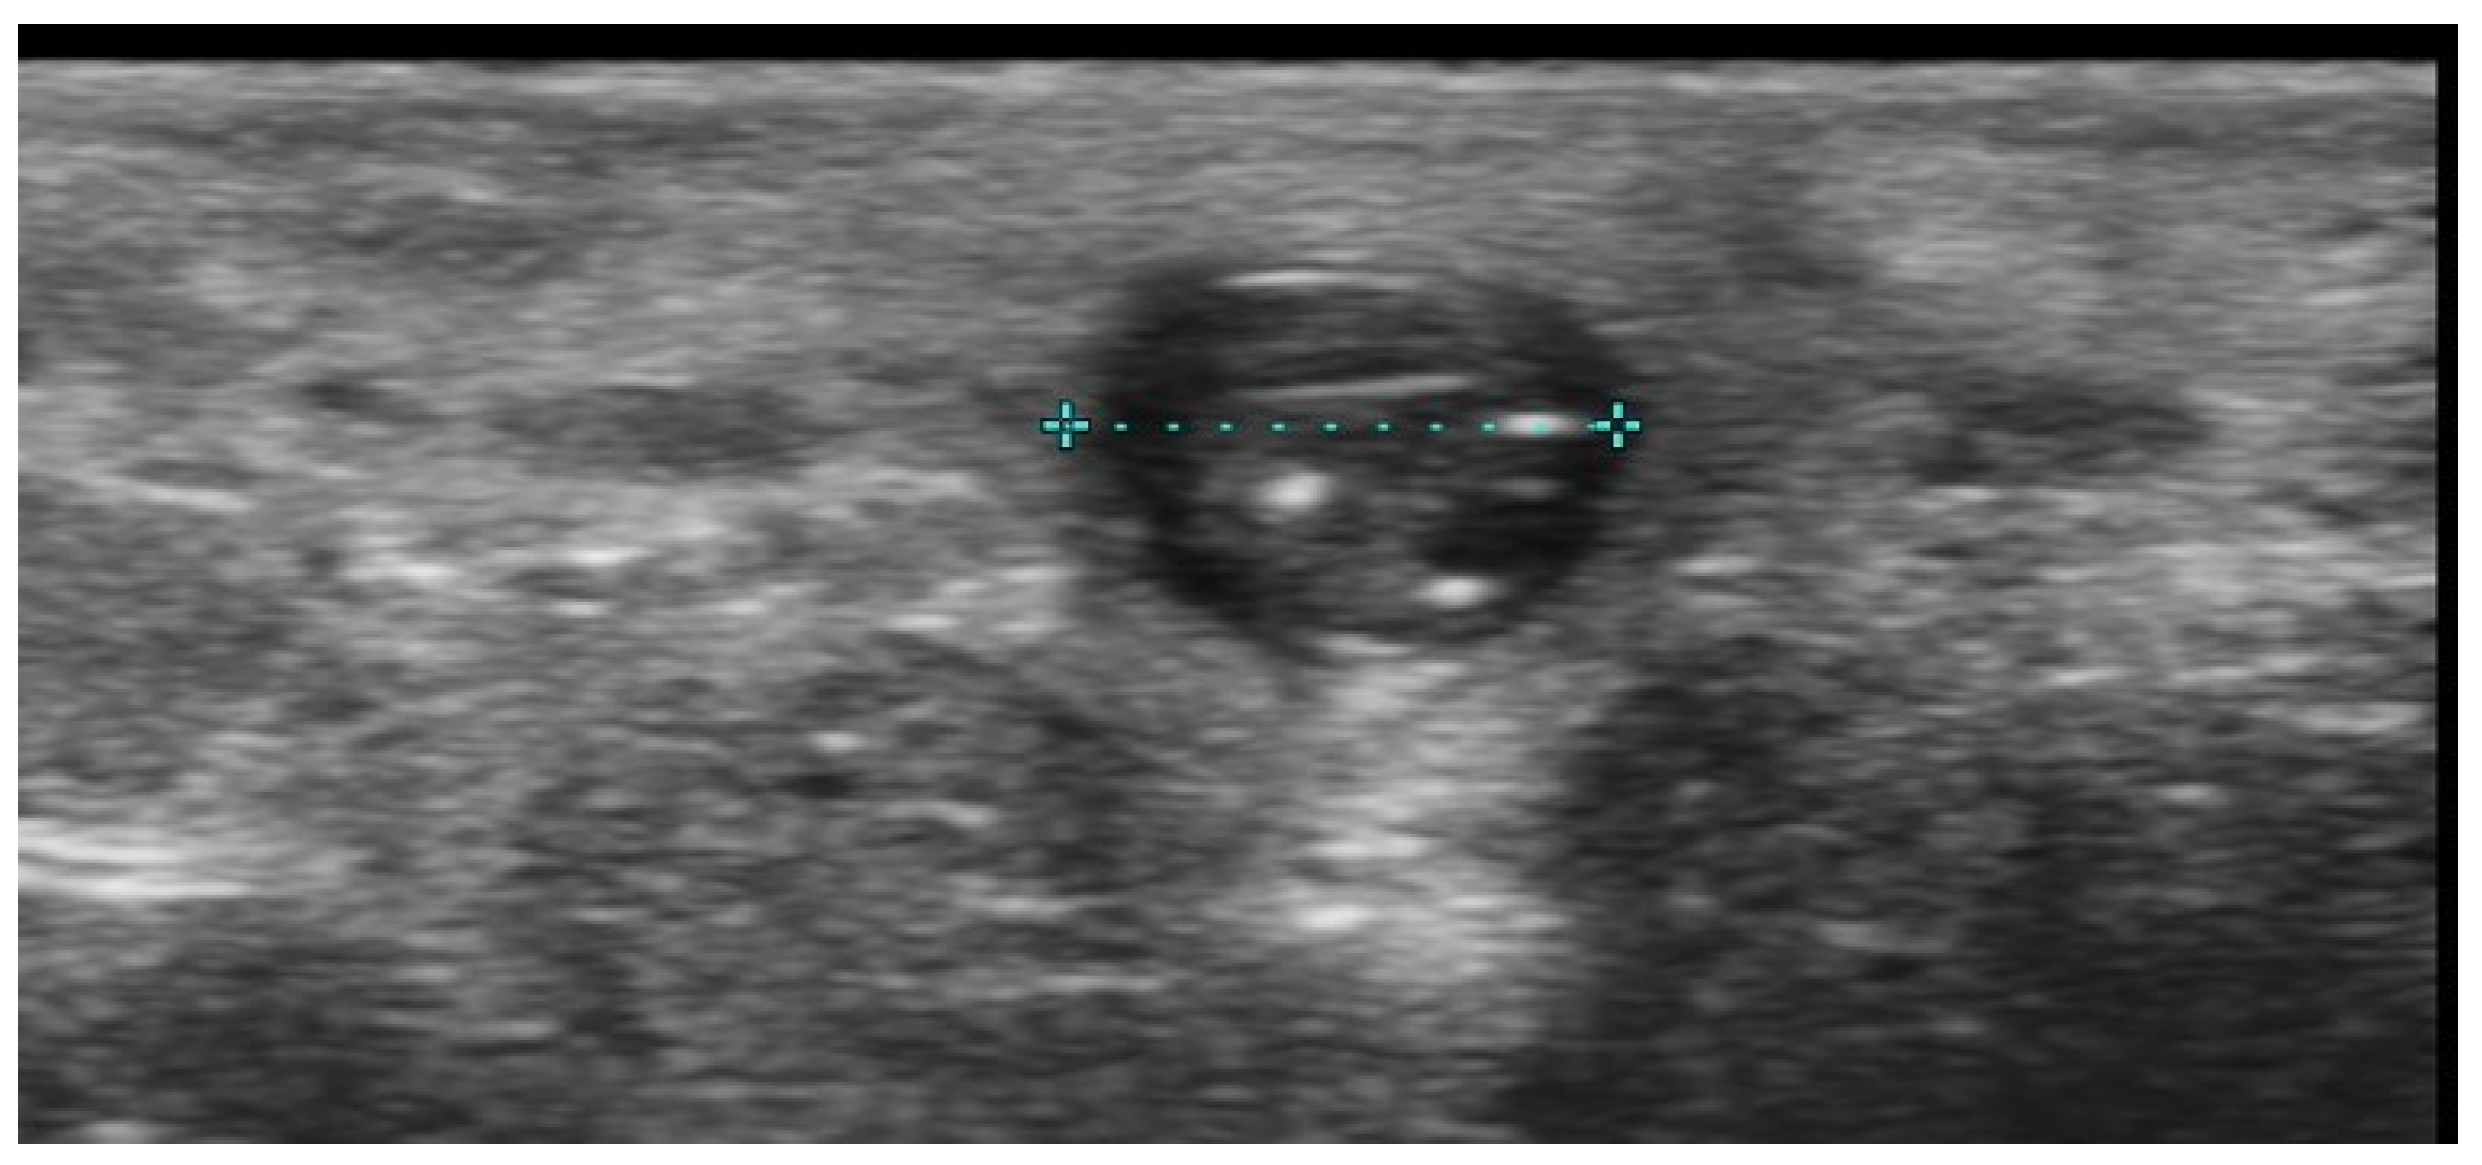

- Hayashi, A.; Giacalone, G.; Yamamoto, T.; Belva, F.; Visconti, G.; Hayashi, N.; Handa, M.; Yoshimatsu, H.; Salgarello, M. Ultra High-frequency Ultrasonographic Imaging with 70 MHz Scanner for Visualization of the Lymphatic Vessels. Plast. Reconstr. Surg. Glob. Open 2019, 7, e2086. [Google Scholar] [CrossRef] [PubMed]

- Cowan, R.; Mann, G.; Salibian, A.A. Ultrasound in Microsurgery: Current Applications and New Frontiers. J. Clin. Med. 2024, 13, 3412. [Google Scholar] [CrossRef]

- Visconti, G.; Hayashi, A.; Bianchi, A.; Tartaglione, G.; Bartoletti, R.; Salgarello, M. Lymphaticovenular Anastomosis for Advanced-Stage Peripheral Lymphedema: Expanding Indication and Introducing the Hand/Foot Sign. J. Plast. Reconstr. Aesthetic Surg. 2022, 75, 2153–2163. [Google Scholar] [CrossRef]